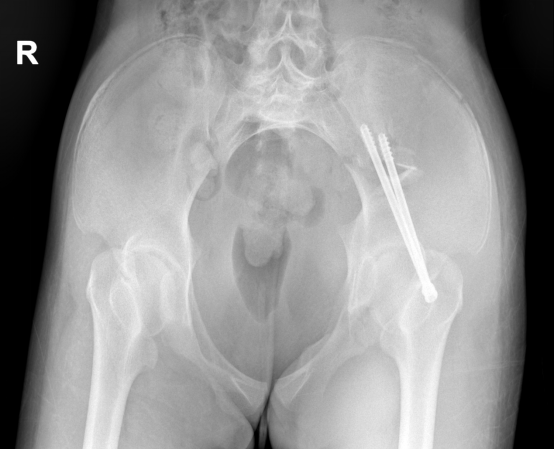

由于在传统手术方式中,为确保骨折固定置入螺钉位置的准确性,往往需要作大切口,术中医生还需要反复透视定位查看置钉位置,不仅创伤大、时间长,X线辐射暴露次数也很多。因此,团队为菲菲制定了微创手术方案,术中团队精准定位、精细操作,手术切口仅2厘米,出血不到10ml,一期为菲菲完成了左侧骨盆骨折内固定手术,术后恢复顺利。

▲术后X片